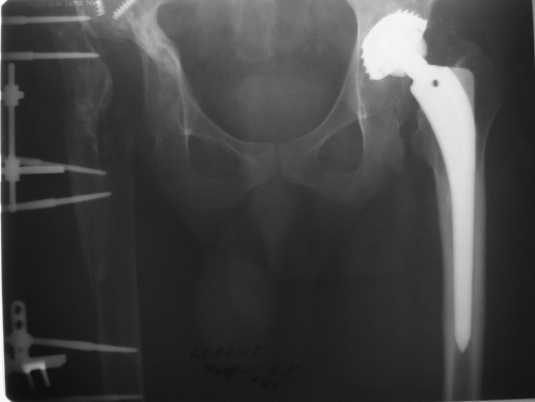

1999г. ревизионное протезирование правого ТБС и вновь инфекционная нестабильность - протез удален.2000 г. установлено кольцо Мюллера и ножка типа Споторно справа (рис. 1).